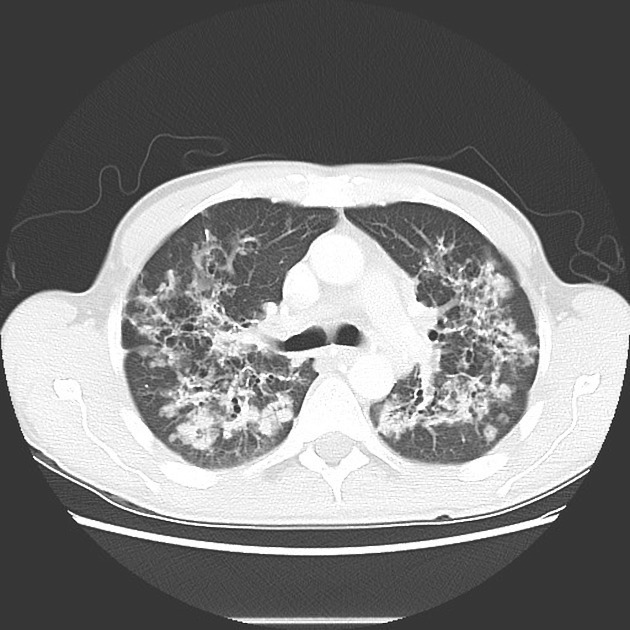

HOMEM, 50 ANOS, INTERNADO POR DISPNEIA + HEMOPTISE DE INÍCIO SÚBITO

áreas de opacidade em vidro fosco associadas a espessamento de septos interlobulares e intralobulares

HEMORRAGIA PULMONAR